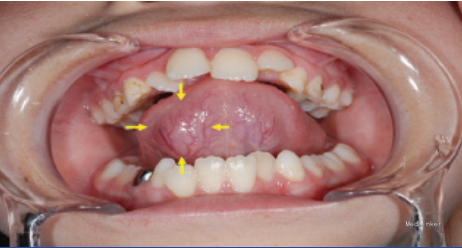

患者八岁,发现舌部有一逐渐生长的肿物一个月,没有其他不适。患者患有共济失调 - 毛细血管扩张症。

检查发现舌下有一隆起,约1.2*1cm大小,未影响舌功能和运动,唾液分泌正常,周围淋巴结无肿大。 影像检查显示右舌有一不规则圆形肿物,边界不清。